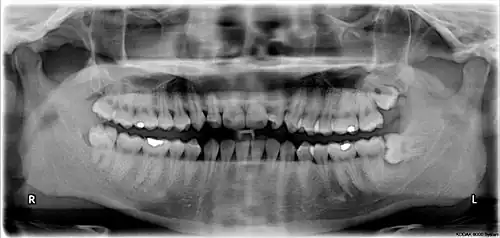

Risk factors of inferior alveolar nerve damage

Temporary and permanent inferior alveolar nerve (IAN) damage is a known complication of the surgical removal of impacted lower third molars, happening in 1 in 85 patients and 1 in 300 extractions, respectively. Studies have shown that certain risk factors may increase the likelihood of IAN damage. Proximity of the impacted third molar root to the mandibular canal, which can be seen in radiographs, has been shown to be a high-risk factor for IAN damage. Alongside this, the depth of impaction of the tooth, surgical technique and surgeons experience are all contributing risk factors for IAN damage during this procedure. Careful case-by-case consideration is crucial to avoid this risk.[44]